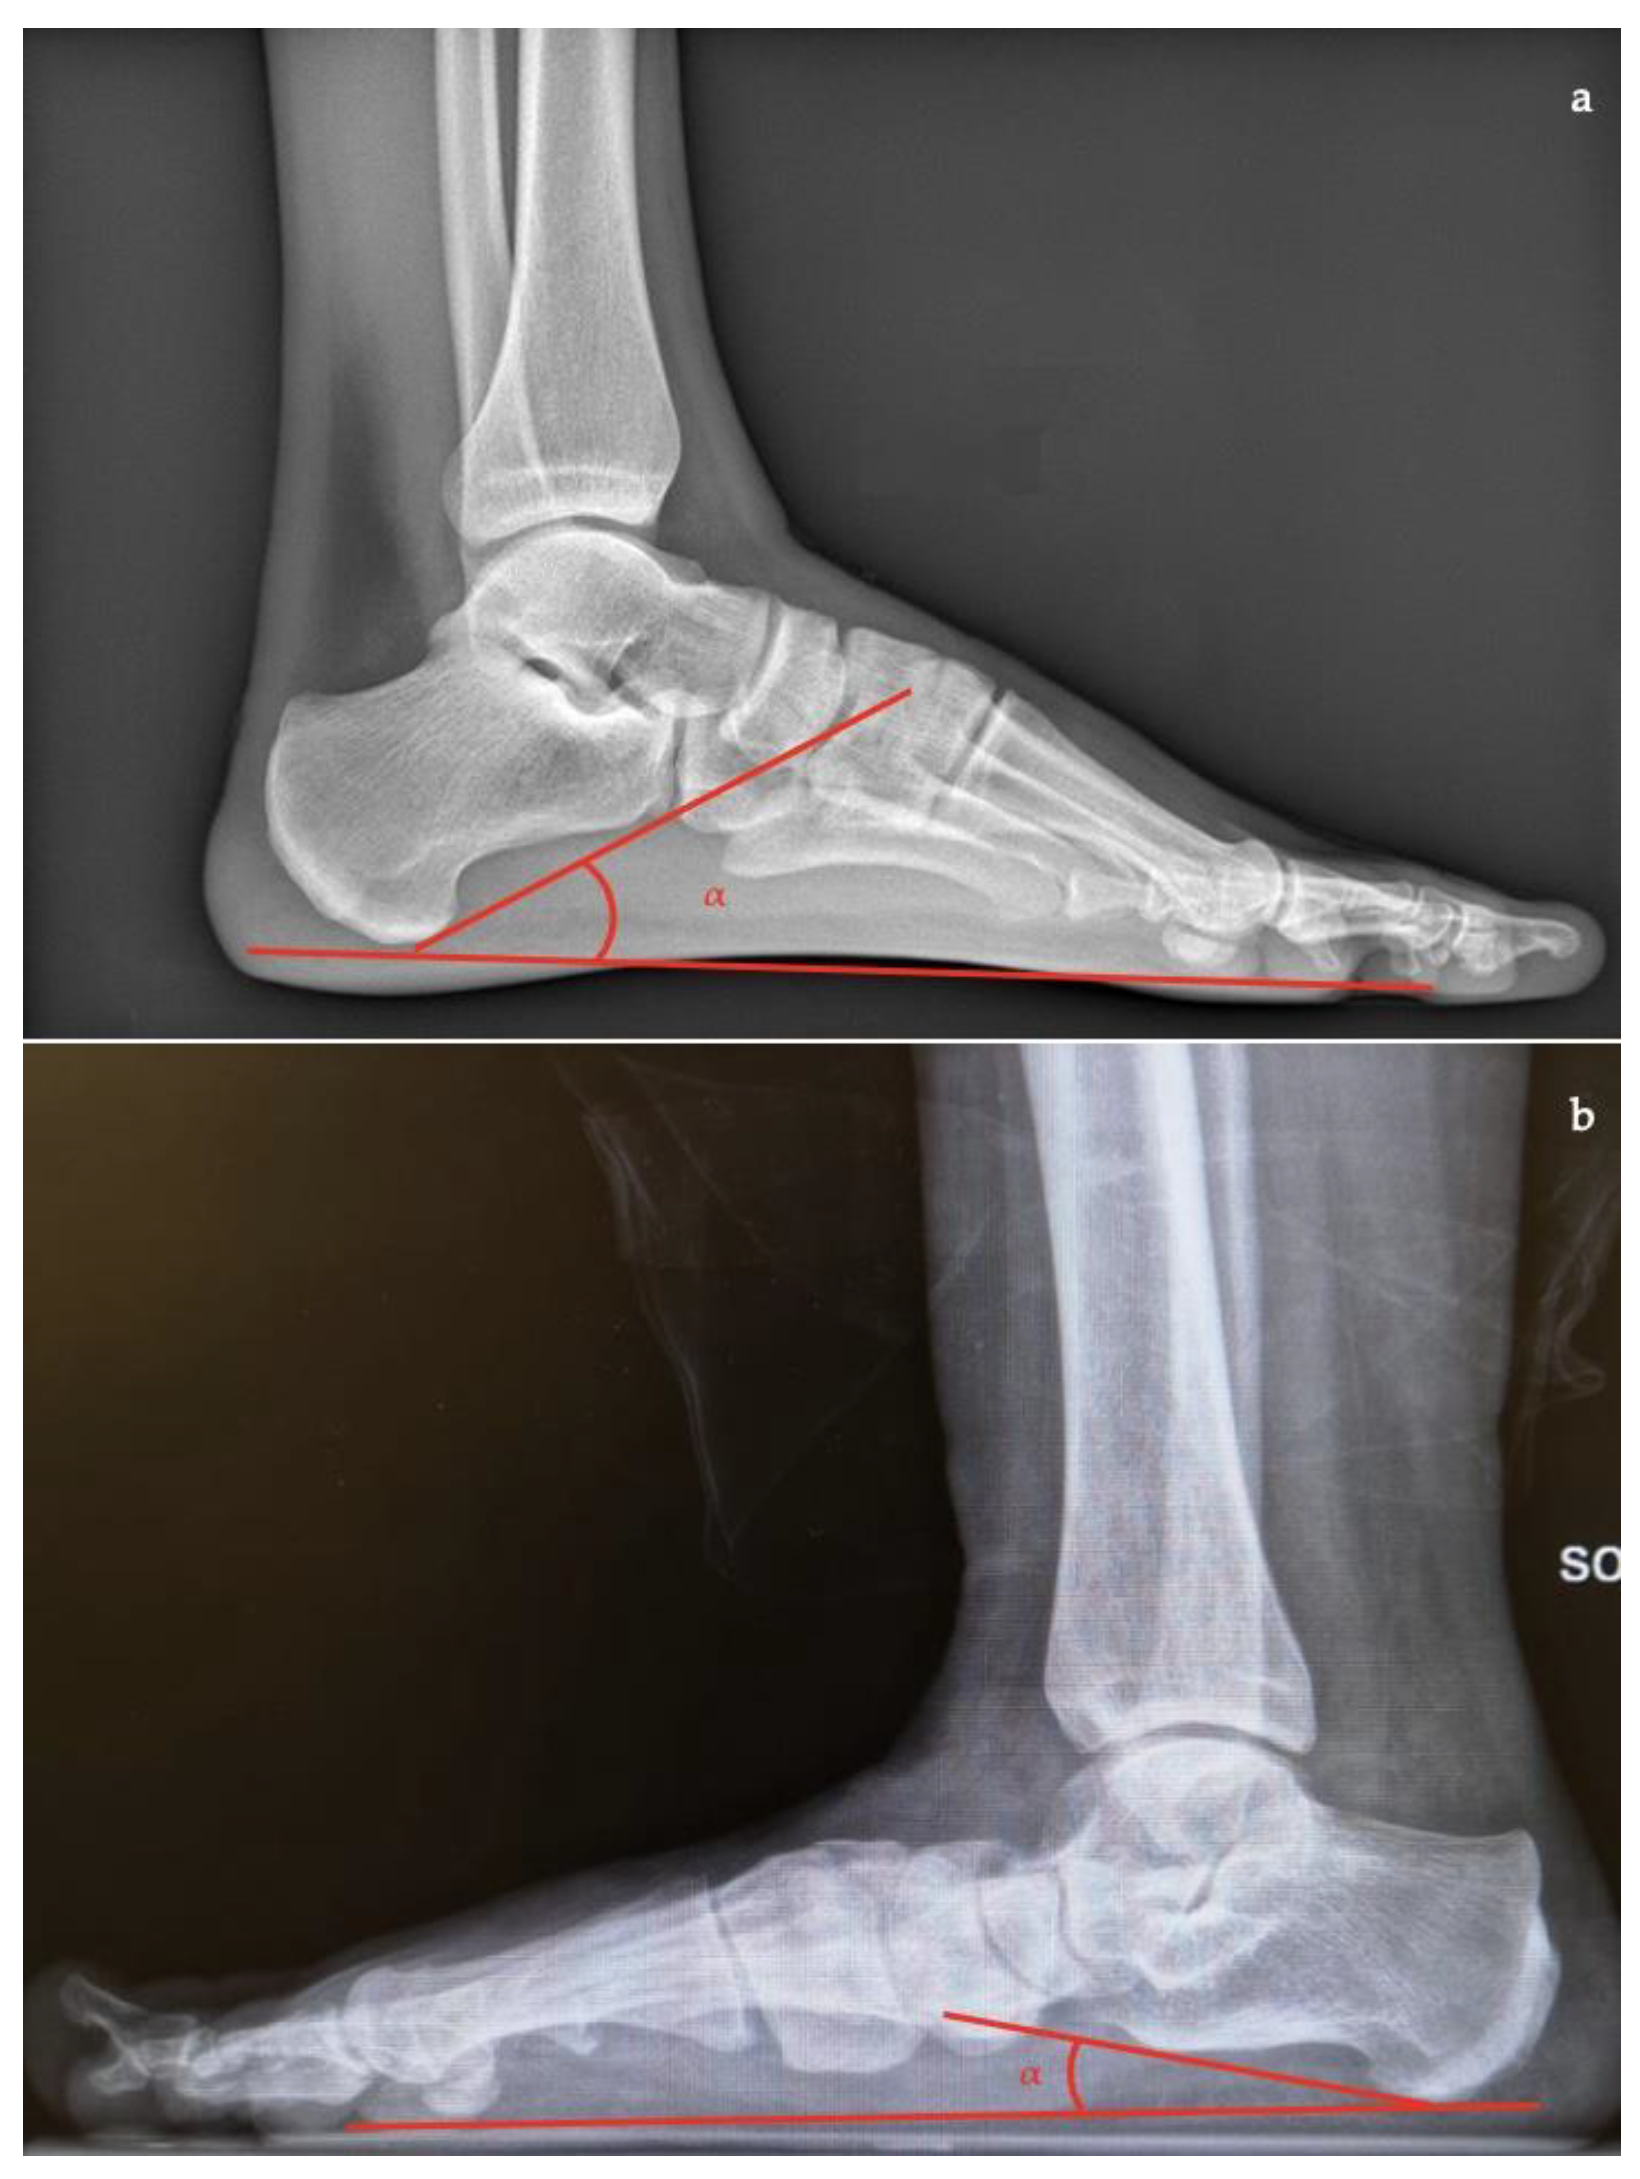

- Talar–first metatarsal angle (Meary’s angle), the normal value is 0 ± 10 degrees and is increased in flatfoot deformity (often >20°, apex directed plantarly) (Figure 5);

- Calcaneal pitch, the angle between the line parallel to the ground and the line along the inferior inclination axis of the calcaneus (normal, 20–30°; flatfoot, <20°) (Figure 6);